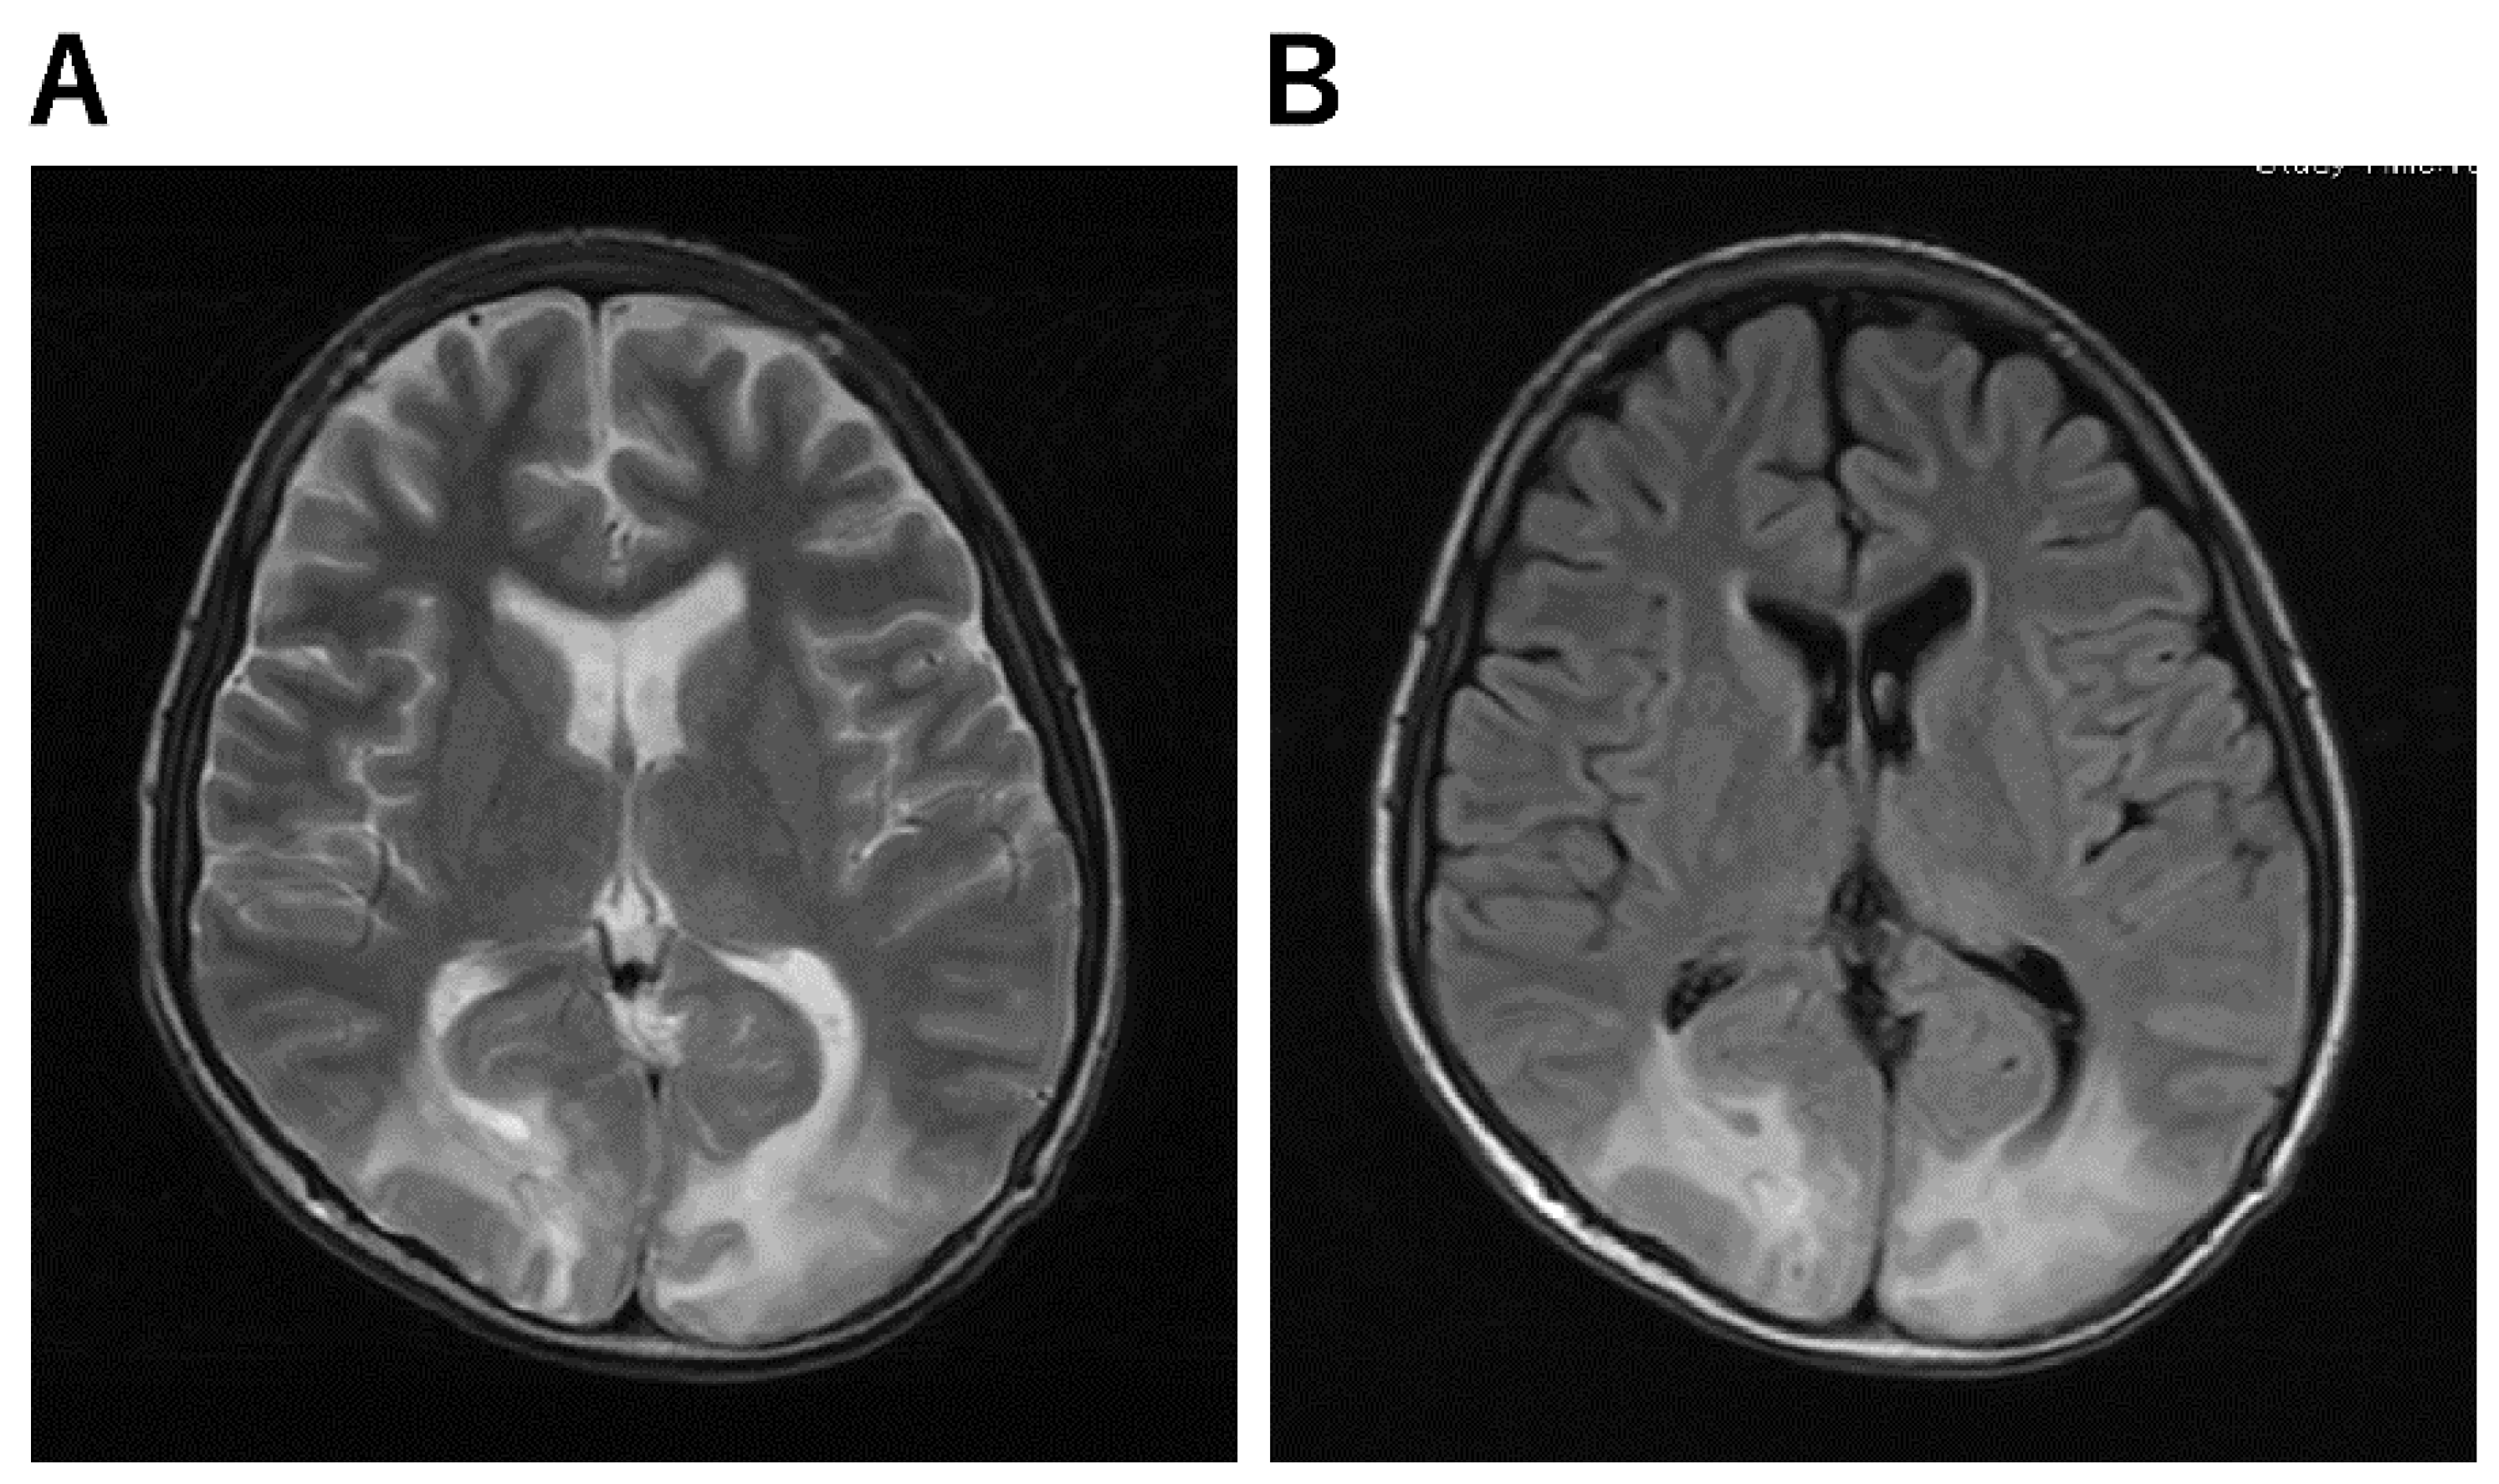

| Clinically mild encephalitis/encephalopathy with a reversible splenial lesion (MERS) [54,55] | a. MRI-DWI shows abnormal signals in the vast portion of the corpus callosum. b. Abnormal intensities in the splenium on ADC-map, FLAIR, T1, and T2-weighted images. |

| Posterior reversible encephalopathy syndrome (PRES) [24,56] | a. Abnormal lesions in the occipital and parietal lobe areas. b. Extensive signal abnormality in the bilateral cerebellar hemispheres and within the thalami. c. T2-FLAIR images show signal abnormality within the midbrain, pons, and superior cerebellar peduncles. c. Fluid-sensitive MR sequences: parieto-occipital predominant white matter T2 hyperintensities |

| MERS [85,86,87] | ||||

| An infection-associated encephalitis/encephalopathy syndrome that is predominately caused by a virus or a variety of pathological conditions, including MIS-C. There have been scattered reports of MERS associated with AFBN and Kawasaki disease. AFBN + MERS, a urinary tract infection in children, is particularly noteworthy | Fever, headache, neck rigidity, and Kerning sign (+) | serum VCA IgG (+), EBNA-1 IgG (−), EBV IgM (−), and inflammation in the analysis of CSF Cranial MRI+C showed that the blood vessels on the surface of the brain were increasing and thickening, and diffuse slow waves were detected on the EEG The high-signal intensity in the splenium of the corpus callosum on T2W Splenial hyperintensity as a “boomerang sign” on DWI and reduced diffusion on ADC | Supplementation, steroids and IVIG, acyclovir, and prescribed oral sodium, but some cases improve with the natural course of the disease. | |

| PRES [56] | ||||

| A clinical–radiological syndrome characterized by a headache, seizures, altered mental status, visual loss and white matter vasogenic edema affecting the posterior occipital and parietal lobes of the brain predominantly. | Visual disturbance can vary from blurred vision and homonymous hemianopsia to cortical blindness. Altered consciousness may vary from mild confusion or agitation to coma. | The bilateral occipital, parietal, frontal cortex, and subcortical white matter T2/fluid-attenuated inversion recovery hyperintensities | Intravenous fluids, antibiotics, antiepileptics | |